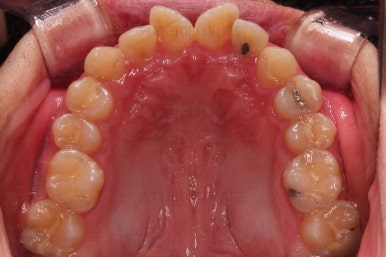

초진 시, 입안의 모습입니다.

치아를 모두 담기에 골격이 매우 작았어요.

이런 경우 치열이 ㅃ뚤어지거나 입이 튀어나오거나 뻐드렁니가 되거나 특정 치아가 묻혀버리거나 맨 뒤치아가 마치 사랑니처럼 올라오지 못한다거나 등등의 문제가 생기는데요.

이번 환자분은 전반적으로 삐뚠 상황이었어요.

앞니도 대칭적으로 삐뚤어져 흔히 나비치아라고 하는 형태로 보이고, 아랫니들은 U자 아치의 형태가 찌그러져 있네요.

당연히 교합도 맞지 않고요.